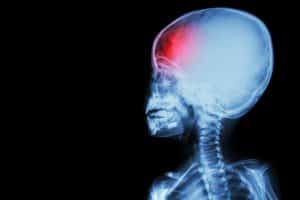

The Ongoing Effects of Severe Pediatric Brain Injury

Brain injuries are a serious concern for individuals of any age, and can be even more severe and life-threatening to children. Pediatric brain injuries can escalate to permanent disability or death.

If you are a parent of a child who suffered a severe pediatric brain injury, you should know what type of long-term, ongoing effects your child might experience for the next few months or even years.